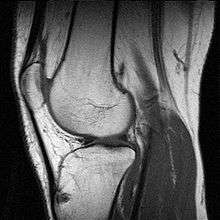

Image from an MRI examination of the knee

MRI uses strong magnetic fields to align atomic nuclei (usually hydrogen protons) within body tissues, then uses a radio signal to disturb the axis of rotation of these nuclei and observes the radio frequency signal generated as the nuclei return to their baseline states.[4] The radio signals are collected by small antennae, called coils, placed near the area of interest. An advantage of MRI is its ability to produce images in axial, coronal, sagittal and multiple oblique planes with equal ease. MRI scans give the best soft tissue contrast of all the imaging modalities. With advances in scanning speed and spatial resolution, and improvements in computer 3D algorithms and hardware, MRI has become an important tool in musculoskeletal radiology and neuroradiology.

One disadvantage is the patient has to hold still for long periods of time in a noisy, cramped space while the imaging is performed. Claustrophobia severe enough to terminate the MRI exam is reported in up to 5% of patients. Recent improvements in magnet design including stronger magnetic fields (3 teslas), shortening exam times, wider, shorter magnet bores and more open magnet designs, have brought some relief for claustrophobic patients. However, for magnets with equivalent field strengths, there is often a trade-off between image quality and open design. MRI has great benefit in imaging the brain, spine, and musculoskeletal system. The use of MRI is currently contraindicated for patients with pacemakers, cochlear implants, some indwelling medication pumps, certain types of cerebral aneurysm clips, metal fragments in the eyes and some metallic hardware due to the powerful magnetic fields and strong fluctuating radio signals to which the body is exposed. Areas of potential advancement include functional imaging, cardiovascular MRI, and MRI-guided therapy.